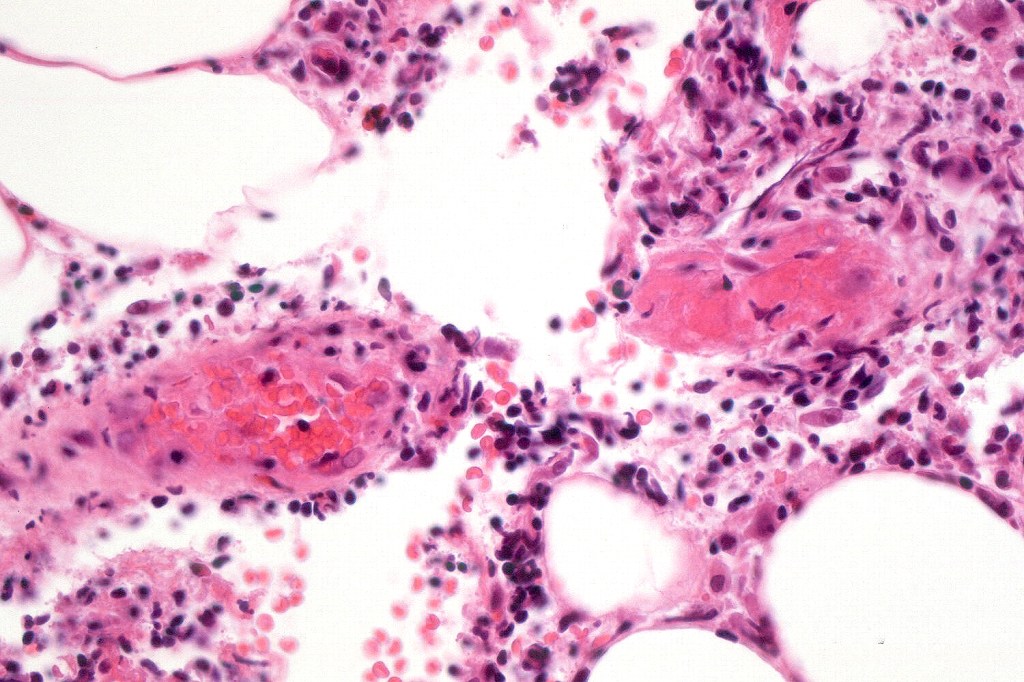

•Type A: 75-80%, wedge shaped infiltrate with base uppermost, large, anaplastic cells with abundant cytoplasm and vesicular nuclei containing prominent nucleoli, can resemble Reed-Sternberg cells, conspicuous mitoses & background infiltrate of lymphocytes, plasma cells, histiocytes, neutrophils & eosinophils

•Variable epidermal necrosis, epidermotropism, edema, hemorrhage & vasculitis/thrombosis